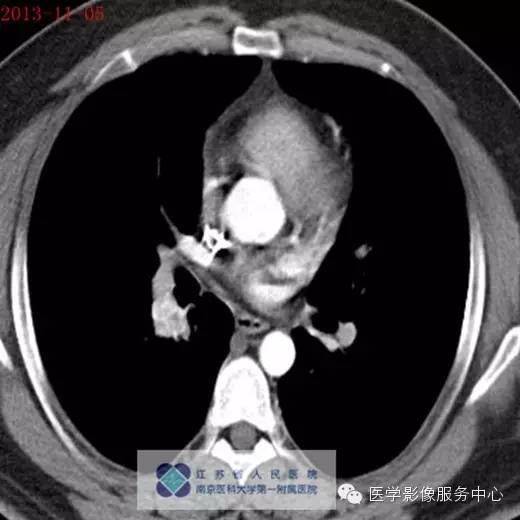

2013年11月5号

影像分析:右侧肺门处见小团块状密度增高影,密度尚均匀,边缘毛糙,增强扫描病灶不均匀强化。

病理:肺神经内分泌瘤